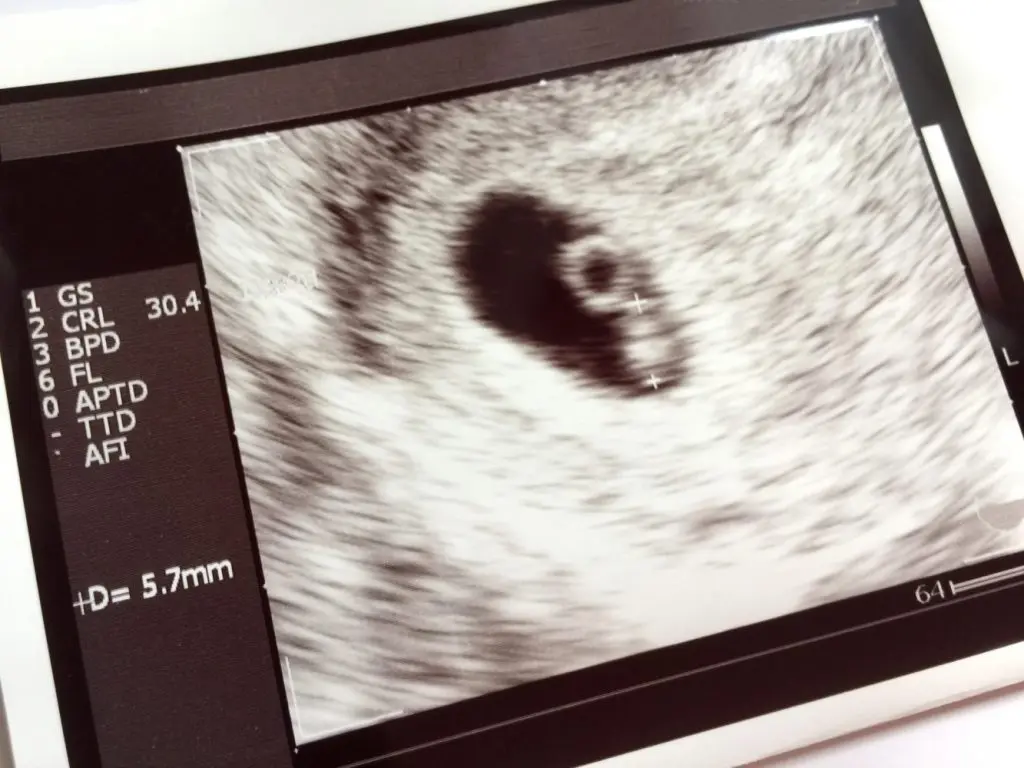

妊娠6週のエコー 胎児の体長は5.7mmです。